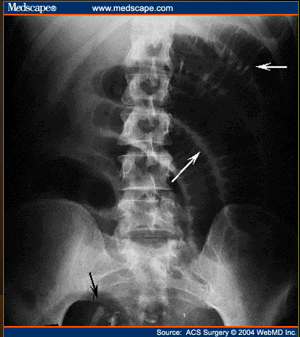

What does this show?

complete small bowel obstruction showing multiple air-fluid levels of varying size arranged in inverted U’s.